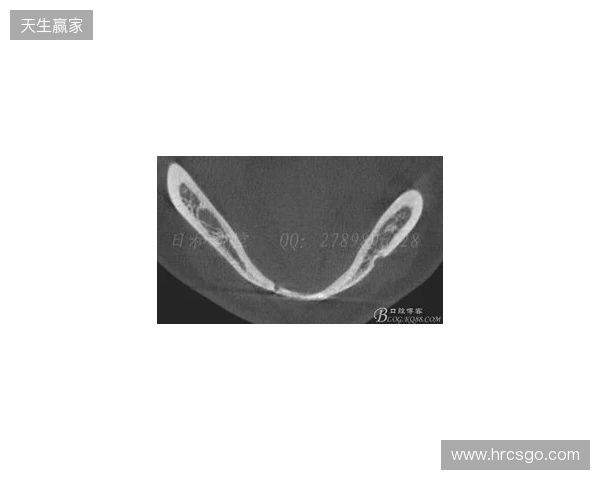

韦林顿确诊上唇部贯通伤;11、21牙半脱位;上颌前牙区牙槽骨骨折

根据医院的检查结果,韦林顿·席尔瓦的上唇部受伤程度较为严重,属于贯通伤,已经进行了清创缝合。这种类型的伤势不仅影响外观,还可能对球员的饮食和发声造成影响。更为严重的是,他的上颌前牙区还出现了骨折,意味着席尔瓦在恢复期间将面临长时间的治疗和康复过程。

球员的第11和第21牙出现了半脱位的情况,这可能会导致他在恢复后需要进行进一步的牙科治疗,甚至有可能影响到他今后的职业生涯。医生表示,虽然通过手术和治疗可以恢复,但心理层面的恢复同样重要。